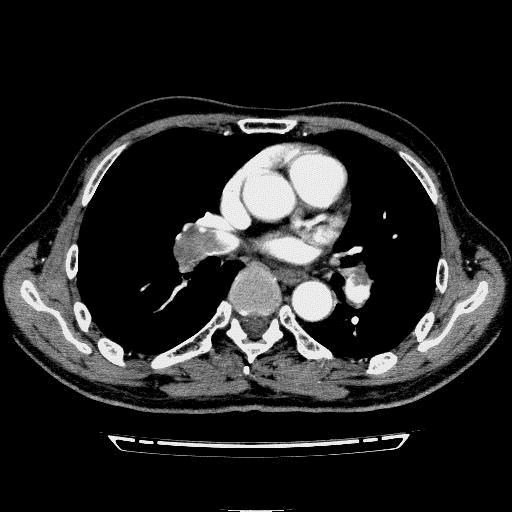

问题 病历摘要: 患者女性,83岁,活动后气促10天,伴心悸、咳嗽,咳少许白粘痰,感左侧胸痛,呈压榨样,与呼吸有关,但无放射痛,并发热,体温最高37.9℃,无明显规律性,无咯血、畏寒等。既往有系统性红斑狼疮病史,有吸烟史20年,已经戒烟20年。1月前始自觉双下肢易疲劳,但活动不受限。体查:T37.7℃,左肺可闻及啸鸣音和少许细湿啰音,心率123bpm,律齐,P2>A2,未闻及杂音。双下肢无水肿。 肺血栓栓塞症的血栓大部分来源于何处? 提示:双下肢静脉超声见双下肢静脉血栓形

选项 A.上腔静脉 B.右心腔 C.下肢近端深静脉 D.盆腔静脉 E.颈内静脉 F.锁骨下静脉 G.肺动脉

答案 C